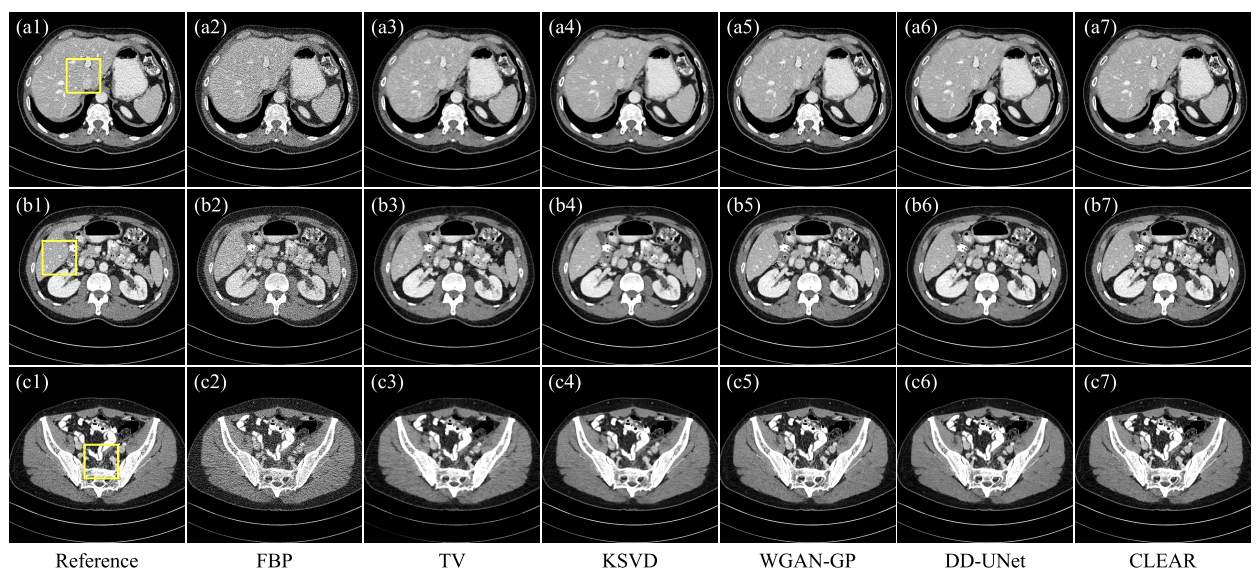

- 비교 모델: FBP, TV(반복 재구성 방법), KSVD(딕셔너리 학습 알고리즘), WGAN-GP(생성 모델을 기반으로 한 후처리 기법), DD-UNet(연속된 네트워크 처리 알고리즘)

- AAPM 결과

- FBP: 노이즈에 의해 심각히 저하

- KSVD:미세한 특징을 거의 복원X(a4)

- TV: 노이즈 억제 잘 하지만, artifact가 미세구조를 손상( c4)

- DD-UNet: 유클리드 거리 최소화로 인해 흐림 효과가 발생

CLEAR: 가장 낮은 MAE, 높은 SSIM,PSNR

- 실제 데이터

- FBP: 노이즈는 이미지의 미세한 특징을 심각하게 손상

- TV: 블록 artifact 발생( c3)

- KSVD: 흐림효과, 미세한 구조 손실(d4)

- DD-UNet:노이즈 억제 x, 세부사항 보존 x

- WGAN-GP , CLEAR: 좋은 시각적 인식(CLEAR가 구조적 충실도에서 더 유망한 성능)

- CLEAR: 가장 높은 SSIM과 PSNR,가장 낮은 MAE